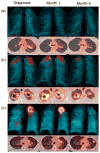

The absence of a gold standard to determine when antibiotics induce a sterilizing cure has confounded the development of new approaches to treat pulmonary tuberculosis (PTB). We detected positron emission tomography and computerized tomography (PET-CT) imaging response patterns consistent with active disease, along with the presence of Mycobacterium tuberculosis (MTB) mRNA in sputum and bronchoalveolar lavage samples, in a substantial proportion of adult, HIV-negative patients with PTB after a standard 6-month treatment plus 1 year follow-up, including patients with a durable cure and others who later developed recurrent disease. The presence of MTB mRNA in the context of nonresolving and intensifying lesions on PET-CT images might indicate ongoing transcription, suggesting that even apparently curative treatment for PTB may not eradicate all of the MTB bacteria in most patients. This suggests an important complementary role for the immune response in maintaining a disease-free state. Sterilizing drugs or host-directed therapies, and better treatment response markers, are probably needed for the successful development of improved and shortened PTB-treatment strategies.